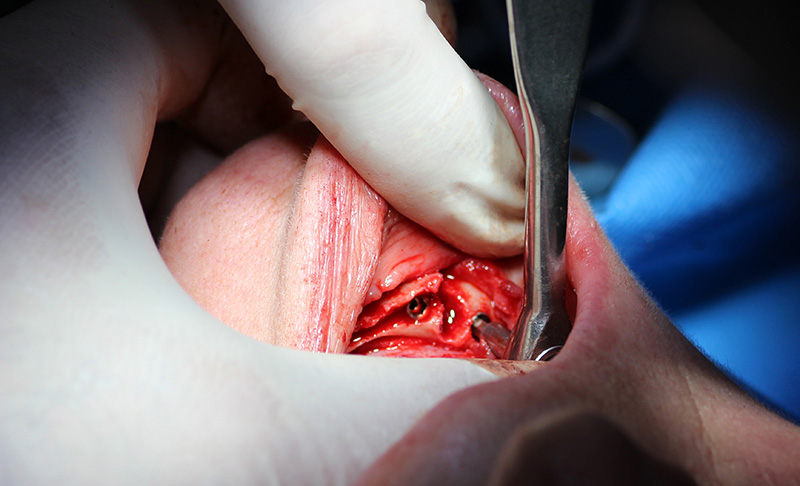

25-ого октября в учебном центре Стом-Лайн был проведен мастер-класс на тему «Одномоментная имплантация с аугментацией (наращиванием) кости, с использованием имплантатов Alfa Gate Dental Implants». Мастер-класс провел главный врач-стоматолог клиники «Нюанс» в Москве Мхитар Казарян.

Мастер-класс начался с обсуждения предстоящей операции и исследования компьютерной томографии, после чего участники смогли присутствовать на операции или следить за ней из учебного центра.